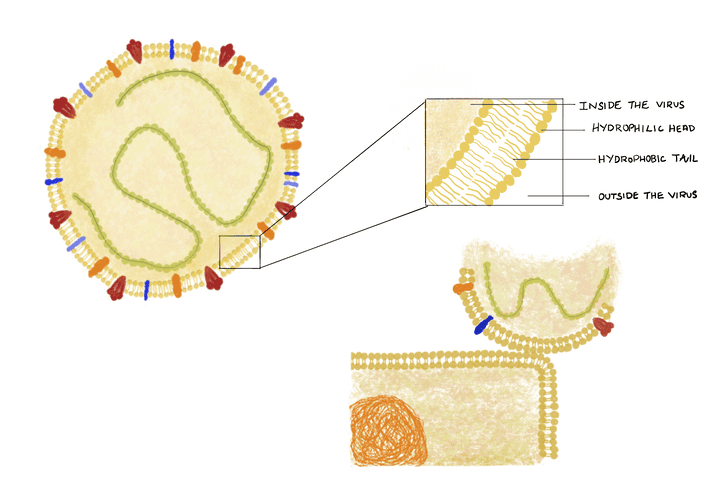

Structure of the coronavirus particle and its interaction with a skin cell. © Sunaina Rao.

Now before we dwell into how we can destroy a virus particle; we first need to understand its structure. The coronavirus, or any other virus for that matter has three main biochemical components:

What’s note worthy here is that human cells, including the ones on the skin, have a similar outer lipid bi layer. This similarity makes it easier for the virus to interact with the cell and stick onto it (Refer image).